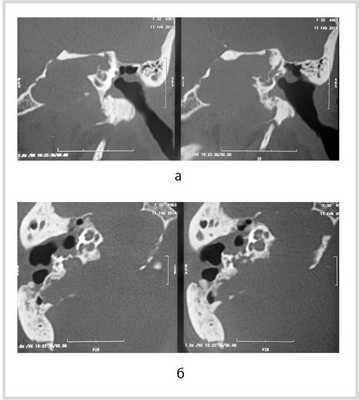

Рис. 1. КТ височных костей пациентки М. а — коронарная проекция: деструктивная полость в пирамиде височной кости, заполненная субстратом неоднородной плотности, капсула лабиринта значительно разрушена на уровне базального и апикального завитков улитки, латерального и верхнего полукружных каналов; б — аксиальная проекция: деструктивная полость с разрушением задней грани пирамиды, передневерхней и нижней поверхности.

МСКТ височной кости — КТ-картина образования пирамиды правой височной кости с костно-деструктивными изменениями, правостороннего среднего отита. Образование на МСКТ височной кости отграничено сверху базальным завитком улитки и преддверием, снизу — яремной веной, медиально — твердой мозговой оболочкой задней черепной ямки, латерально — гипо- и мезотимпанумом, спереди — вертикальной частью внутренней сонной артерии, сзади — сагиттальным ПК, внутренним слуховым проходом (рис. 1). Рис. 1. МСКТ височной кости (правое ухо). КТ-картина инфралабиринтной холестеатомы пирамиды височной кости (а — аксиальная проекция, б — коронарная проекция).